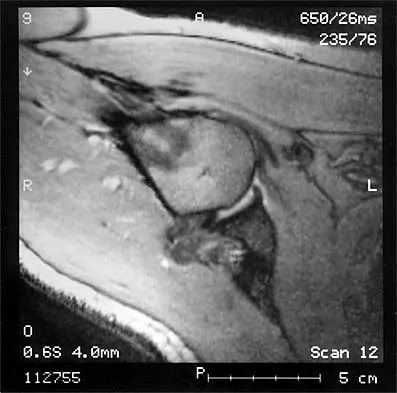

The MRI scan of the shoulder shown in Figure 2 was performed with the arm in abduction and external rotation. The image reveals what condition?